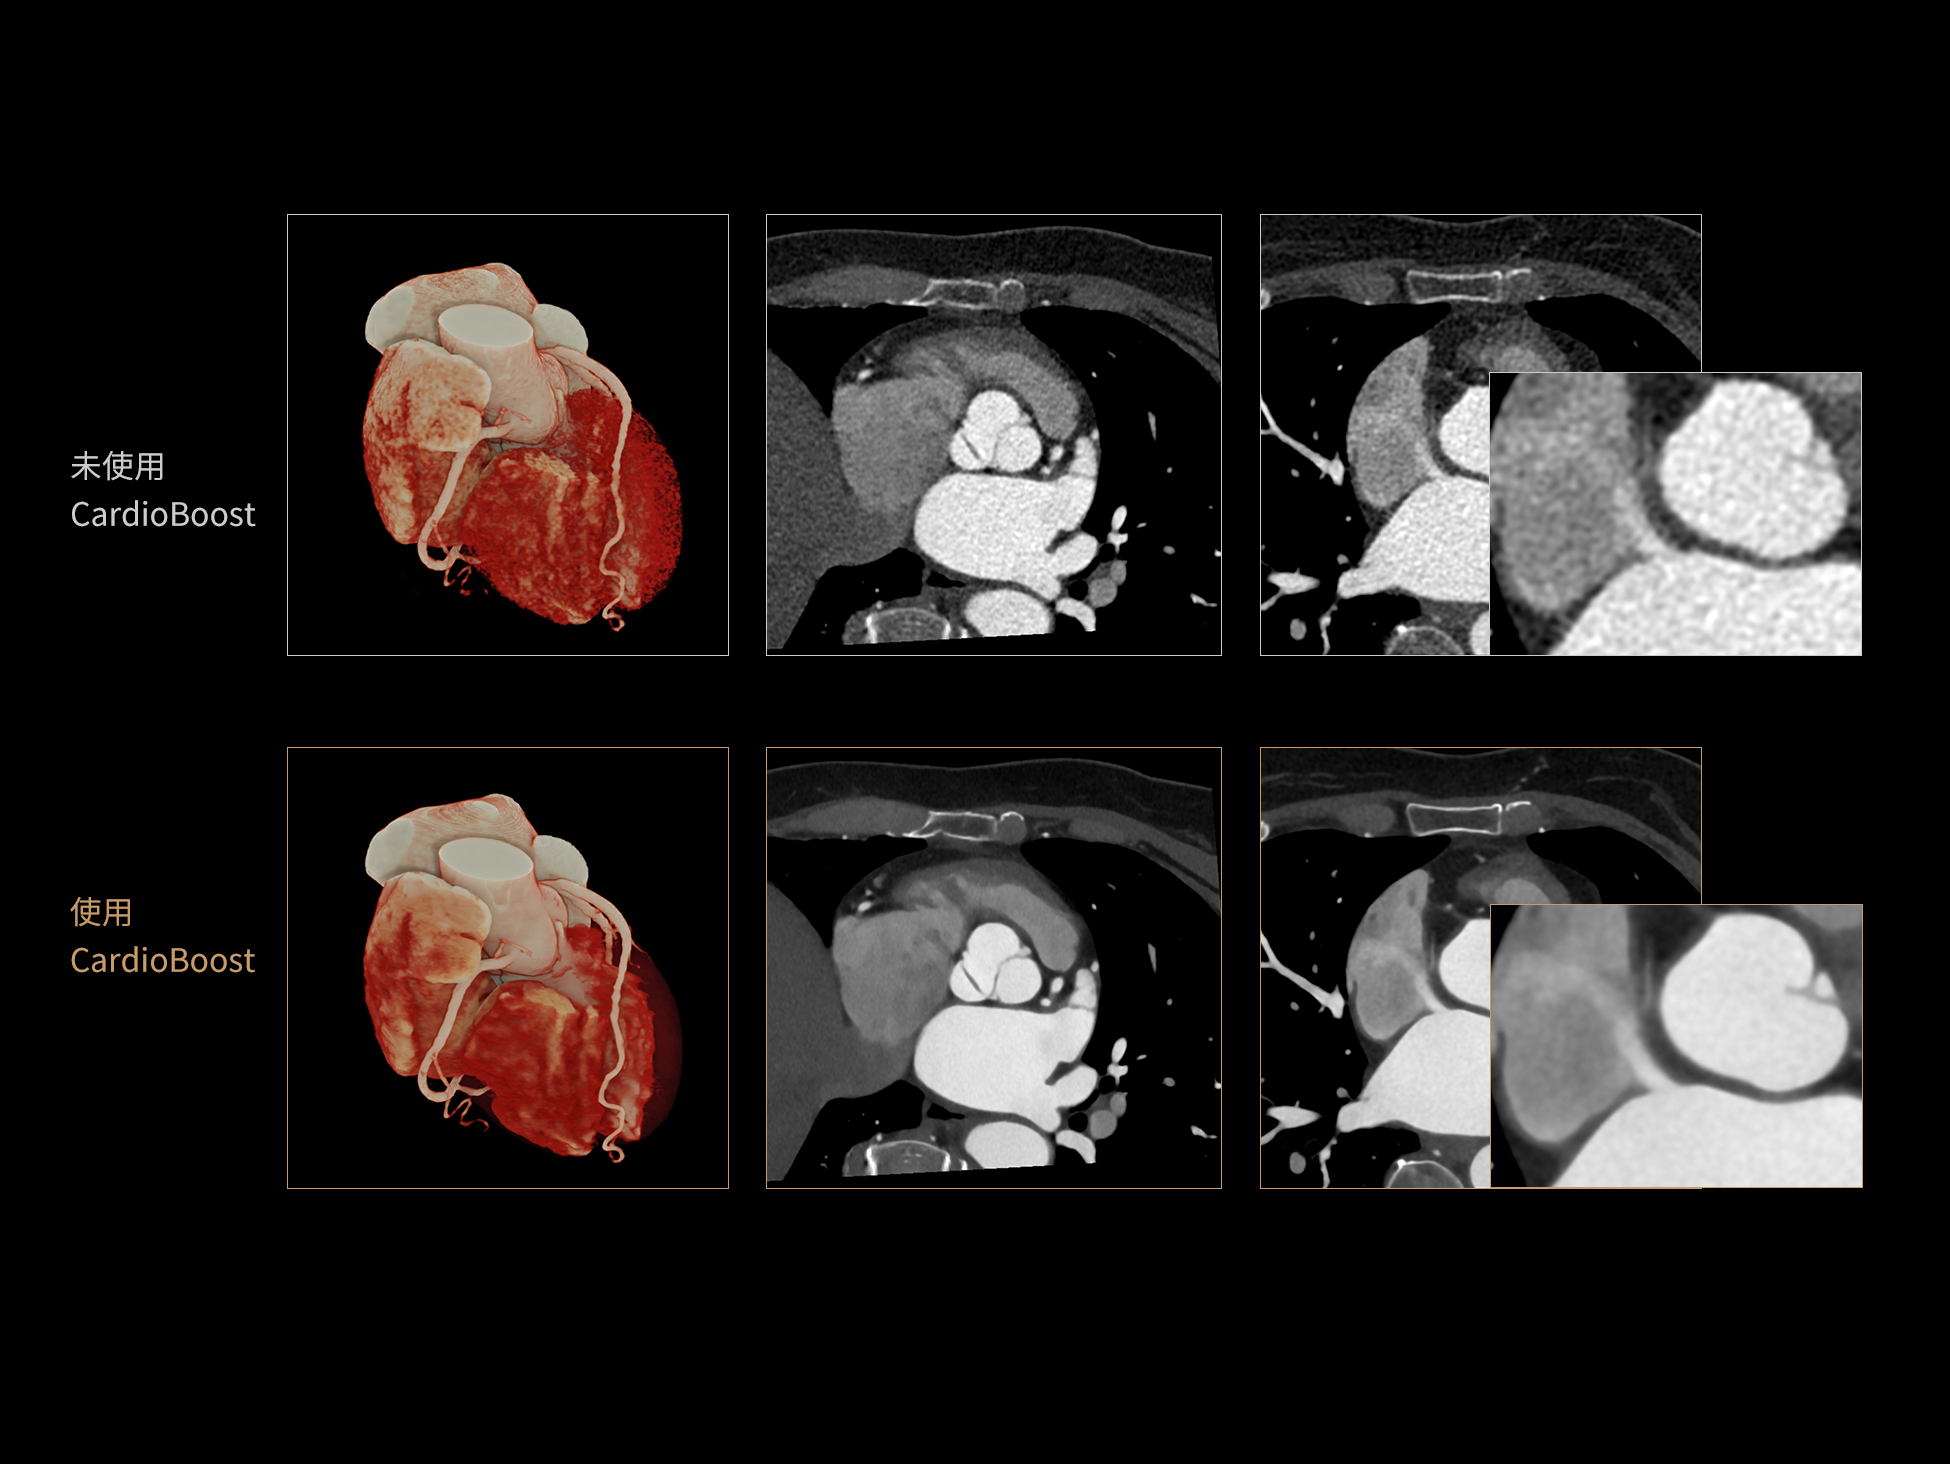

CardioBoost:专属网络设计,重塑心脏影像表现

目前心脏的 CT 检查还存在辐射剂量偏高、空间分辨率不足、 致密钙化伪影影响冠脉狭窄程度评估等方面的限 制[1][2]。CardioBoost 技术专为心脏 CT 高清成像而开发,通过 3D 神经网络的深度学习技术,利用先进的注意力机制在识别关键成像特征方面的出色表现,能够精确地聚焦于斑块、支架以及微小血管等关键细节,清晰展示这些结构与冠脉血管的边界,从而显著提高诊断的准确性,并提升医生的诊断信心。创新的 CardioBoost 心脏图像重建算法,不仅实现了图像清晰度的提升和伪影的去除,更能在减少辐射剂量的同时,保证心脏图像的高质量和图像纹理的自然。

采用 3D 神经网络的空间结构优势与精细的组织分类能力,CardioBoost 技术优化了组织对比,高清展示血管斑块,使斑块与血管边缘的轮廓清晰可辨,提升斑块诊断与评估的精确性。

借助 3D 神经网络设计、空间注意力机制聚焦与特征强化作用,CardioBoost技术提升图像的空间分辨率,实现冠脉支架的高清成像,对支架形态与管腔通畅度的评估更精准。

CardioBoost 整合先进的 3D 神经网络和空间注意力机制,大幅增强数据处理的速度与精确度。该技术能有效抑制由致密钙化引起的晕状伪影,清晰展现钙化斑块的原始结构和大小,对冠脉狭窄的评估更加精确可靠。

对比度强化模块

分辨率强化模块

伪影抑制模块